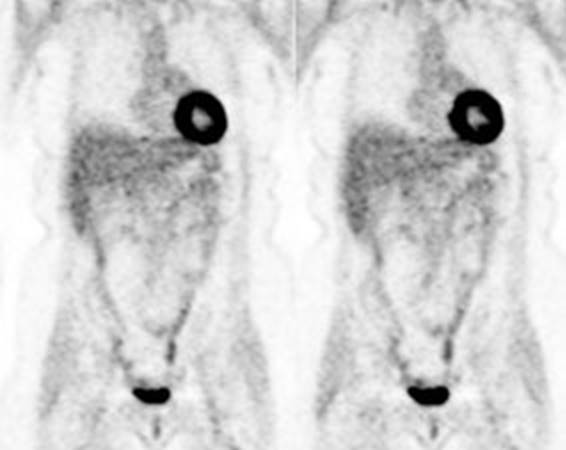

Figure 2 - Normal

brain activity: The image below demonstrates normal FDG brain activity.